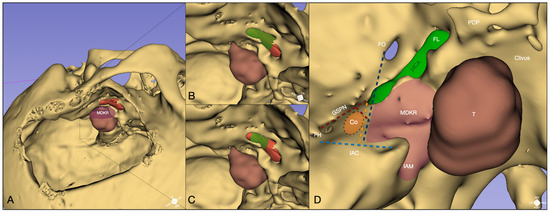

3.1. Cadaveric Simulation